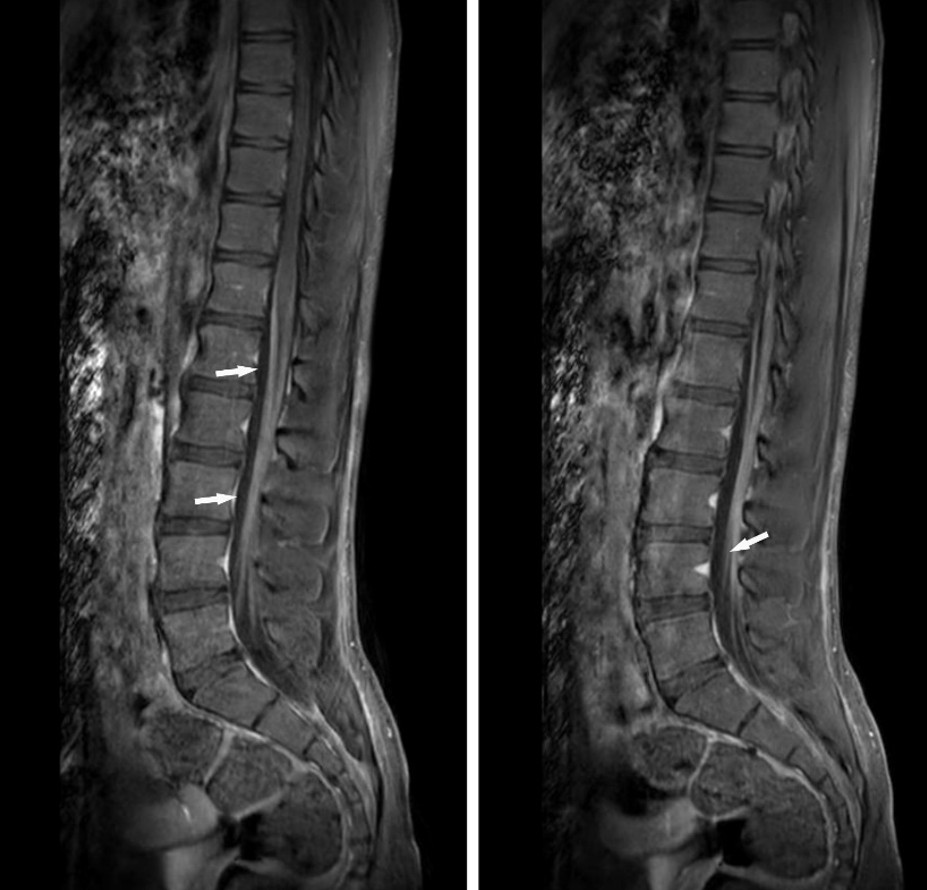

Spinal MRI with contrast revealed pathological enhancement of the cauda equina nerve roots in the sagittal sequence, further supporting the diagnosis (Figure 1). Cerebrospinal fluid (CSF) analysis via lumbar puncture demonstrated albuminocytologic dissociation: elevated protein level (57 mg/dL; reference range: 15–45 mg/dL) with no white blood cells. CSF glucose was within normal limits. No oligoclonal bands were detected, and polymerase chain reaction (PCR) testing was negative for herpes simplex virus, varicella zoster virus, and enterovirus. Serologic evaluations for coeliac disease, paraneoplastic syndromes, and anti-ganglioside antibodies were also negative.